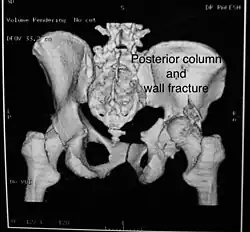

Posterior column and wall fracture as seen on 3D CT -

Posterior column and wall fixed using screws and plates